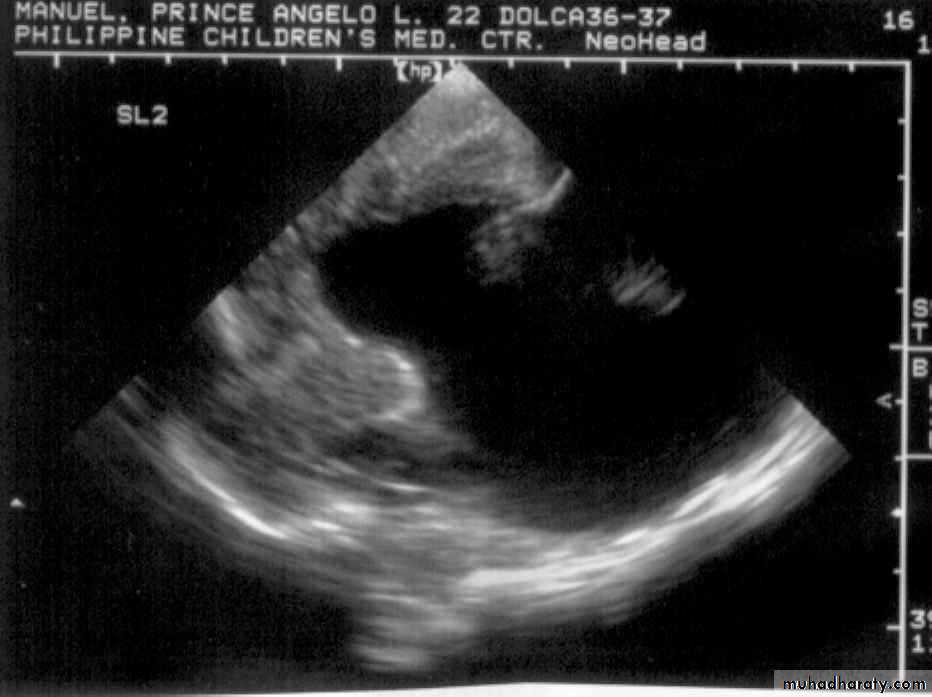

P.M, 22 days old CA 36-37 wks, with cleft lip and palate

Holoprosencephaly, semilobarMacrogyria

Absent Septum Pellucidum

Dysgenesis of the Corpus Callosum